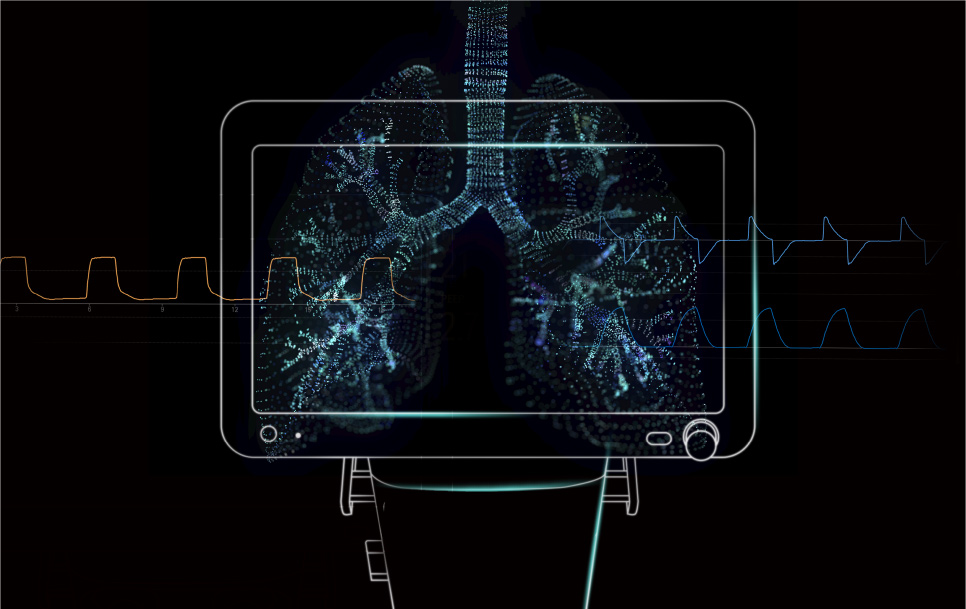

Des Êvolutions importantes peuvent survenir au cours d'une pandÊmie. La communautÊ de la mÊdecine respiratoire a ÊtÊ la première à faire les frais de la pandÊmie, en raison de la forte transmissibilitÊ du virus responsable de la COVID-19 et de la dÊtÊrioration rapide de l'Êtat des patients. Les professionnels de la santÊ ont approfondi le dÊbat sur la facilitÊ d'utilisation, l'efficacitÊ et les caractÊristiques de protection pulmonaire des ventilateurs. ? l'avenir, l'obtention d'un Êquilibre entre sÊcuritÊ et efficacitÊ des ventilateurs utilisÊs en clinique et la rÊduction supplÊmentaire des obstacles à l'utilisation des ventilateurs et à la formation seront des questions incontournables dans le dÊveloppement des ventilateurs pour les soins intensifs dans l'ère post-ÊpidÊmie.

Cependant, avec l'aide de l'Internet des objets, des algorithmes, de l'IA et d'autres technologies avancĂŠes, le monde mĂŠdical vit un moment dĂŠcisif. ? l'avenir, l'innovation dans le domaine des ventilateurs sera axĂŠe sur l'informatisation mĂŠdicale et la prĂŠsence d'intelligence artificielle dans les machines individuelles, ce qui permettra de soulager continuellement la charge du personnel mĂŠdical et de fournir aux patients des traitements plus exacts pour un meilleur rĂŠtablissement.

Se concentrant sur le concept de protection pulmonaire exacte, Mindray s'est efforcÊ de fournir une aide à la dÊcision clinique pour l'ensemble du processus d'intubation, mesure et Êvaluation, aide à la ventilation, extubation, afin d'amÊliorer la sÊcuritÊ clinique. Les outils d'aide à la dÊcision pour les ventilateurs s'appuyent sur l'intÊgration des donnÊes au chevet du patient et sur des algorithmes avancÊs pour aider les cliniciens à Êvaluer les indicateurs du patient de manière plus exhaustive. L'identification des mouvements respiratoires du patient et l'Êvaluation plus exacte de la rÊexpansion pulmonaire permet aux cliniciens de sÊlectionner les traitements les plus adaptÊs pour faciliter le rÊtablissement.

Des dispositifs plus puissants et davantage d'informations ne doivent Êvidemment pas entra?ner des exigences accrues pour les opÊrateurs. Les ventilateurs Êvoluent plut?t vers une ventilation intelligente en circuit fermÊ, tout comme les voitures intelligentes sont sur la voie de la conduite autonome. En rÊalisant progressivement une ??identification automatique?? du schÊma respiratoire du patient et un ??ajustement automatique?? des paramètres de ventilation, les ventilateurs intelligents amÊliorent l'efficacitÊ clinique et la synergie ventilateur-patient. Gr?ce aux ventilateurs intelligents, les soignants peuvent mieux rÊpondre à de nombreuses situations dans les scÊnarios de soins aigus, sous anesthÊsie et de soins intensifs et rÊduire les ajustements rÊpÊtÊs des modes et paramètres de ventilation, afin de mieux garantir la sÊcuritÊ des patients.

Se concentrant sur le concept de protection pulmonaire exacte, Mindray s'est efforcÊ de fournir une aide à la dÊcision clinique pour l'ensemble du processus d'intubation, mesure et Êvaluation, aide à la ventilation, extubation, afin d'amÊliorer la sÊcuritÊ clinique. Les outils d'aide à la dÊcision pour les ventilateurs s'appuyent sur l'intÊgration des donnÊes au chevet du patient et sur des algorithmes avancÊs pour aider les cliniciens à Êvaluer les indicateurs du patient de manière plus exhaustive. L'identification des mouvements respiratoires du patient et l'Êvaluation plus exacte de la rÊexpansion pulmonaire permet aux cliniciens de sÊlectionner les traitements les plus adaptÊs pour faciliter le rÊtablissement.

Des dispositifs plus puissants et davantage d'informations ne doivent Êvidemment pas entra?ner des exigences accrues pour les opÊrateurs. Les ventilateurs Êvoluent plut?t vers une ventilation intelligente en circuit fermÊ, tout comme les voitures intelligentes sont sur la voie de la conduite autonome. En rÊalisant progressivement une ??identification automatique?? du schÊma respiratoire du patient et un ??ajustement automatique?? des paramètres de ventilation, les ventilateurs intelligents amÊliorent l'efficacitÊ clinique et la synergie ventilateur-patient. Gr?ce aux ventilateurs intelligents, les soignants peuvent mieux rÊpondre à de nombreuses situations dans les scÊnarios de soins aigus, sous anesthÊsie et de soins intensifs et rÊduire les ajustements rÊpÊtÊs des modes et paramètres de ventilation, afin de mieux garantir la sÊcuritÊ des patients.